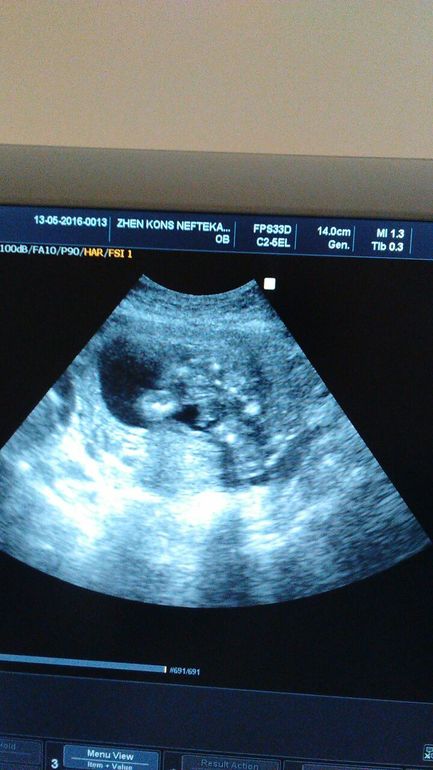

Девочки, не могу понять это писька у нас такая большая или врач не то смотрит? она сказала что мальчик и то что я отметила красным тыпо это две мошонки и по середине писюн. Я просмотрела снимку узи в инете но чет ни у кого мошонки не видела у всех мальчиков виднеется только палочка. думаю может это ножки а не половой орган?